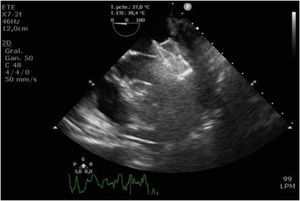

Tras el procedimiento, el paciente fue trasladado al hospital de día donde, a las 2h, inició un episodio de disnea acompañado de náuseas, desaturación e hipotensión. Se detectó una insuficiencia mitral (IM) severa de novo por desplazamiento del dispositivo implantado (figs. 1 y 2). El paciente entró en situación de shock cardiogénico y se trasladó a quirófano de forma emergente.